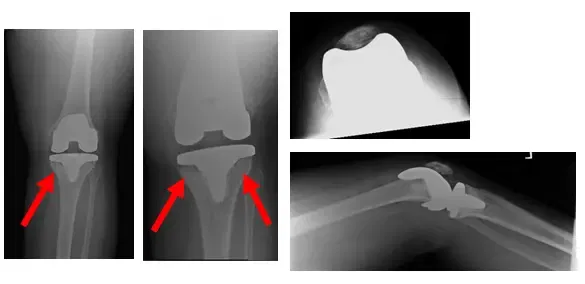

Patient is a 50 year old male who came in complaining of left knee pain. Patient stated that he had received a left Total Knee Arthroplasty (TKA) a few years ago at an outside facility.

Patient presented with a restricted range of motion and was in severe pain. Patient brought in x-rays to review, as shown below.

X-Rays show left total knee replacement with lucency around the tibial component of the prosthesis. Arrows indicate lucency

Upon review, the lucency seen in the X-Rays indicates loosening of the prosthesis. Patient was instructed to have an aspiration and blood work done to check for infection, and results came back negative.

Pre-operative X-rays show osteolysis and loosening of the TKA prosthesis